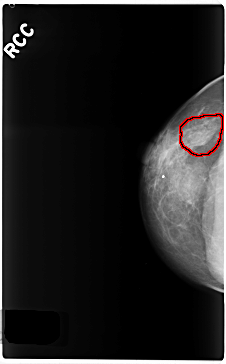

C_0270_1.RIGHT_CC

RIGHT_CC LINES 4720 PIXELS_PER_LINE 2928 BITS_PER_PIXEL 12 RESOLUTION 50 OVERLAY

FILE: C_0270_1.RIGHT_CC.OVERLAY

TOTAL_ABNORMALITIES 1

ABNORMALITY 1

LESION_TYPE MASS SHAPE OVAL MARGINS OBSCURED

ASSESSMENT 3

SUBTLETY 3

PATHOLOGY BENIGN

TOTAL_OUTLINES 1

BOUNDARY